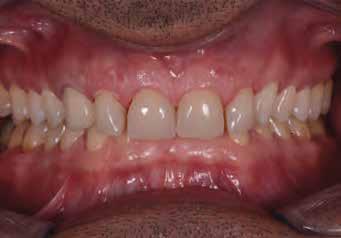

Dr. Marco Nicastro (Olaszország) A kiindulási állapot és a végeredmény. A KATANA™ UTML kiváló esztétikai tulajdonságokkal rendelkezik, és tökéletesen, harmonikusan illeszkedik a rózsaszín szövetekkel.

16. ábra: Klinikai fotó egy évvel a PANAVIA V5-tel történő beragasztás után. A marginális szövetek jó klinikai állapotát látjuk, semmi jele gyulladásnak vagy vérzésnek. A BOPT lehetővé teszi számunkra, hogy optimalizáljuk a gingiva szintjét anélkül, hogy parodontológiai sebészeti beavatkozáshoz folyamodnánk, miközben az új koronák alakja lehetővé tette az interproximális terek zárását az optimális esztétikai eredmény érdekében.

17. ábra: A fogpótlás világossága (főleg a transzlucentes cirkónium használatának köszönhetően), a metszők alakjával kombinálva nagymértékben javította a pótlás esztétikáját, még akkor is, ha a kiindulási helyzet különösen kedvezőtlennek tűnt.

18. ábra: Az előző fogpótlással összehasonlítva a metszők redukálása nem csak azt tette számunkra lehetővé, hogy optimalizáljuk a funkcionális fázist az overjet csökkentésével, hanem lehetővé tette a még esztétikusabb eredmény elérését azzal, hogy a metszők élének kontúrjával követni tudtuk az alsó ajkat.